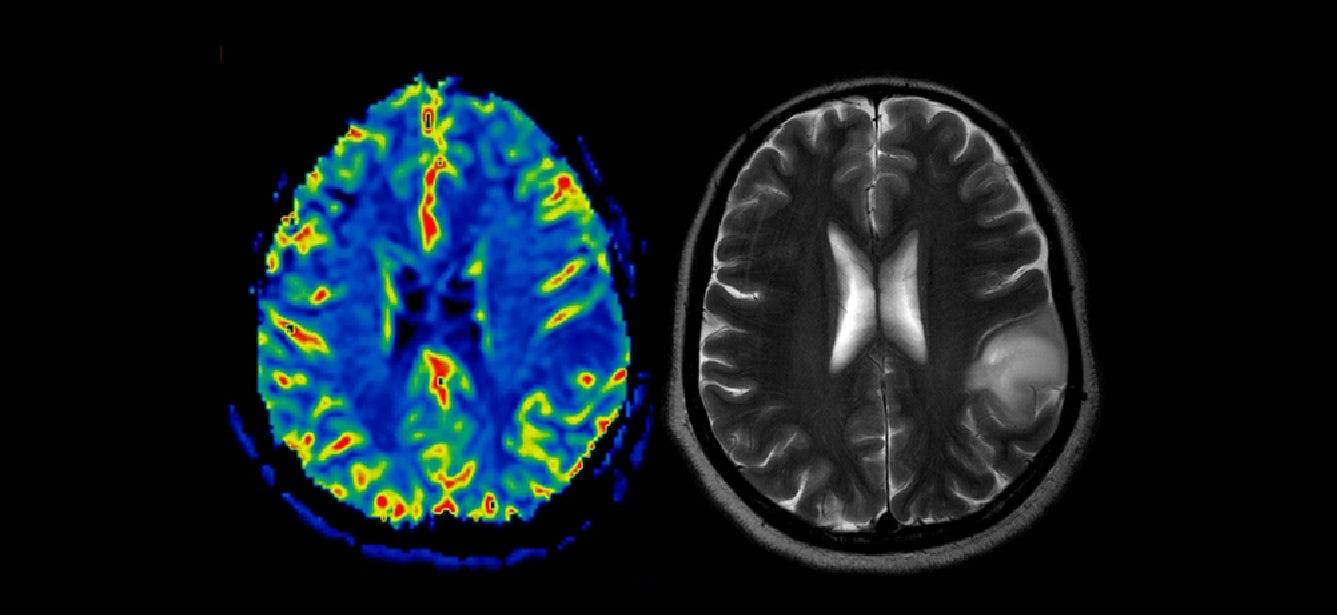

Brain Health

What Is Alzheimer's? How Is It Treated?